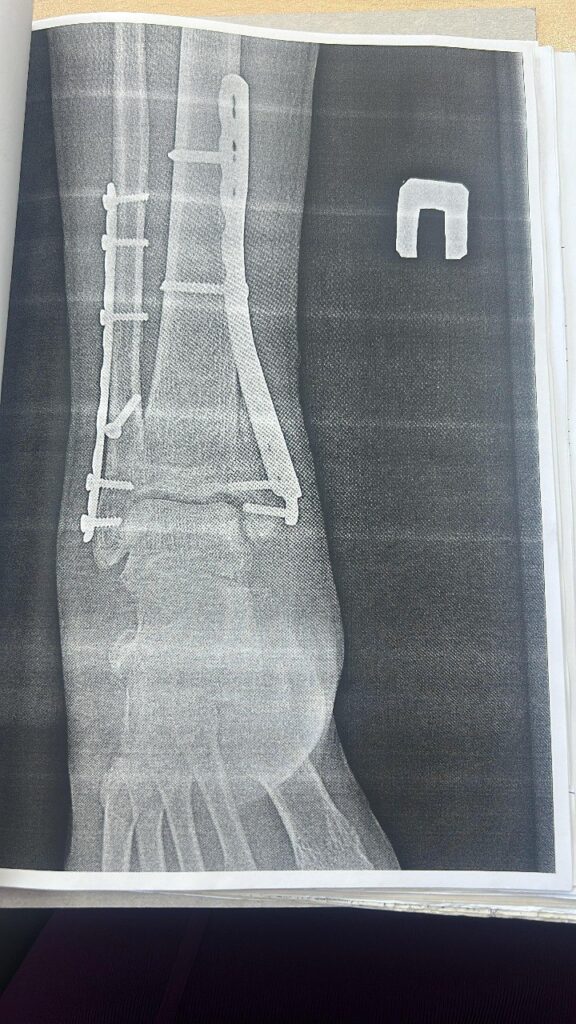

По информации Благовещенского городского суда, упавший возле подъезда на улице Комсомольской горожанин сломал обе лодыжки и вывихнул стопу. Ему пришлось лечь в больницу и долго восстанавливаться.